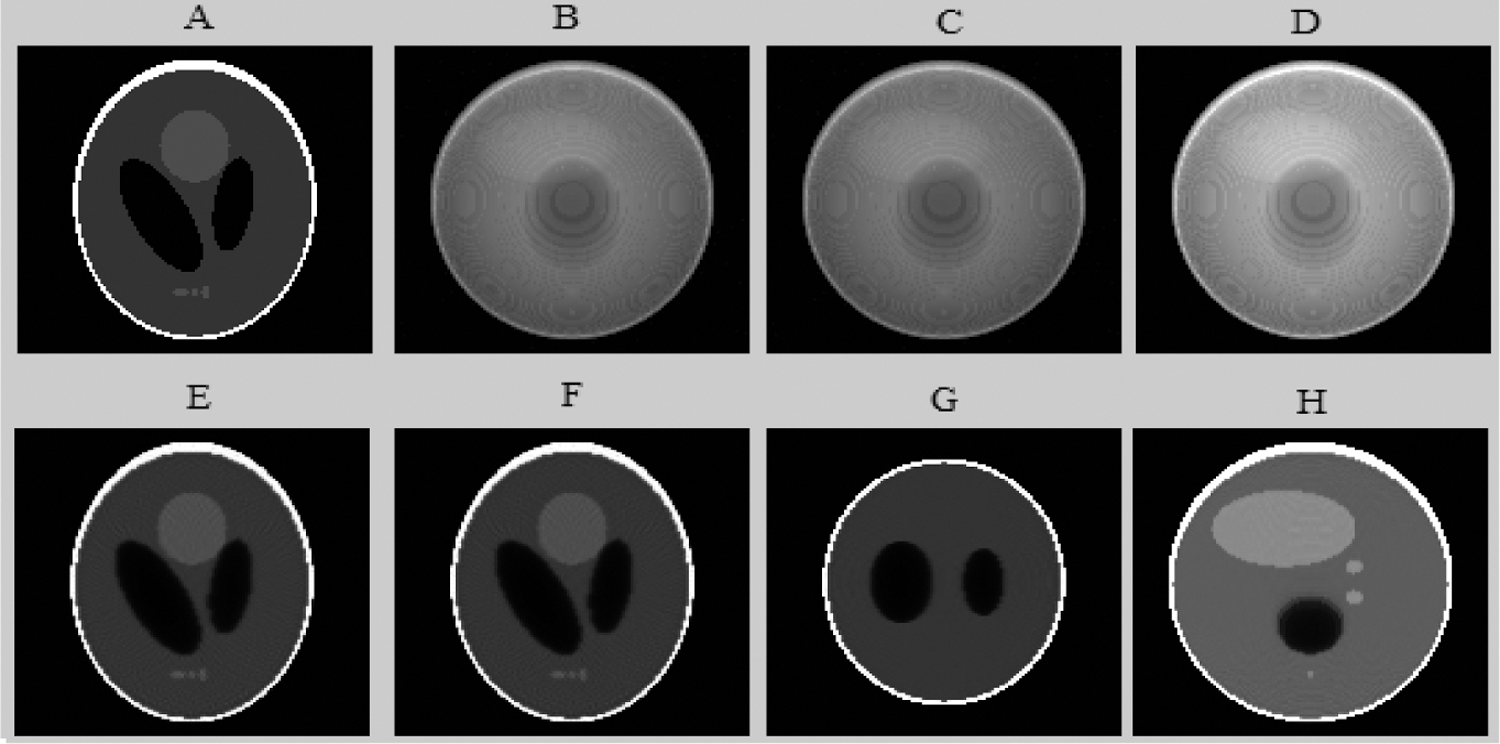

The sequence of Shepp-Logan projections was additionally randomized with a Medium Poisson noise level. The Poisson noise level was used by scaling the sinogram value to 50%. Then, we applied the reconstruction methods to the noisy sequence. To present the phases introduced in Section 2.1, Fig. 8 outlines the different results of the suggested method at a gray level Shepp-Logan phantom image at frame 64. Various parameters were tried to get the highest performance.

Fig. 8 shows the robustness and the accuracy of the proposed algorithm in tomographic reconstruction.

Figure 8: The different results of the proposed algorithm from the tomographic Shepp-Logan Phantom (SLP) image at frame 64. (A) Original (SLP) projection; (B) Noisy (SLP) projection; (C) Projection (SLP) denoised by the Wavelet; (D) Fusion step for (SLP) projection denoising; (E) Reconstructed (SLP) slice; (F) Enhanced axial (SLP) slice by EDP; (G) Coronal enhanced (SLP) slice and (H) Sagittal enhanced (SLP) slice